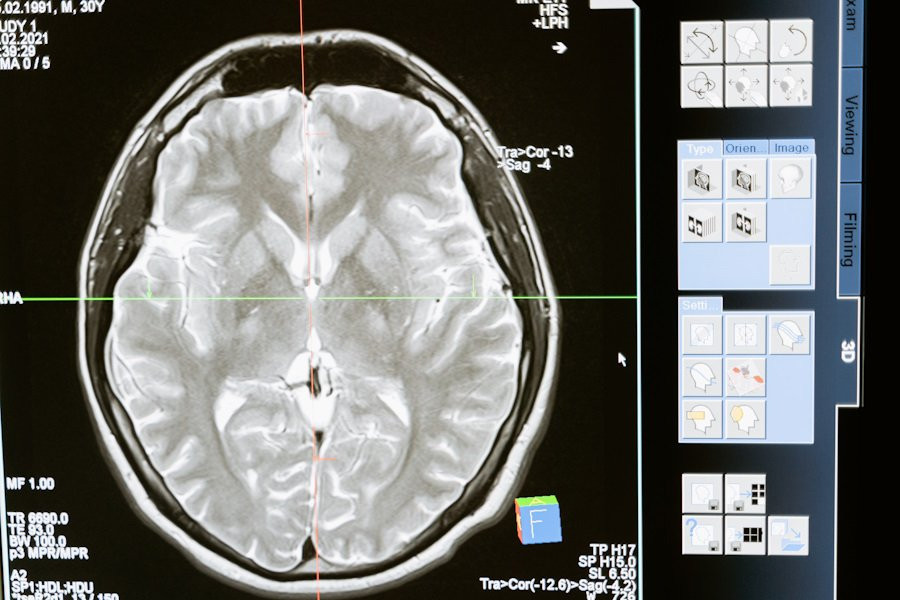

Головной мозг защищен от внешних воздействий с помощью особого барьера — гематоэнцефалического, который не пропускает посторонние вещества. Это сильно затрудняет доставку лекарств, особенно при лечении таких сложных заболеваний, как глиобластома — самый агрессивный вид первичного рака мозга. Но, благодаря работе ученых под руководством профессора Беренда Снейдера, может появиться новый подход к лечению этого заболевания.